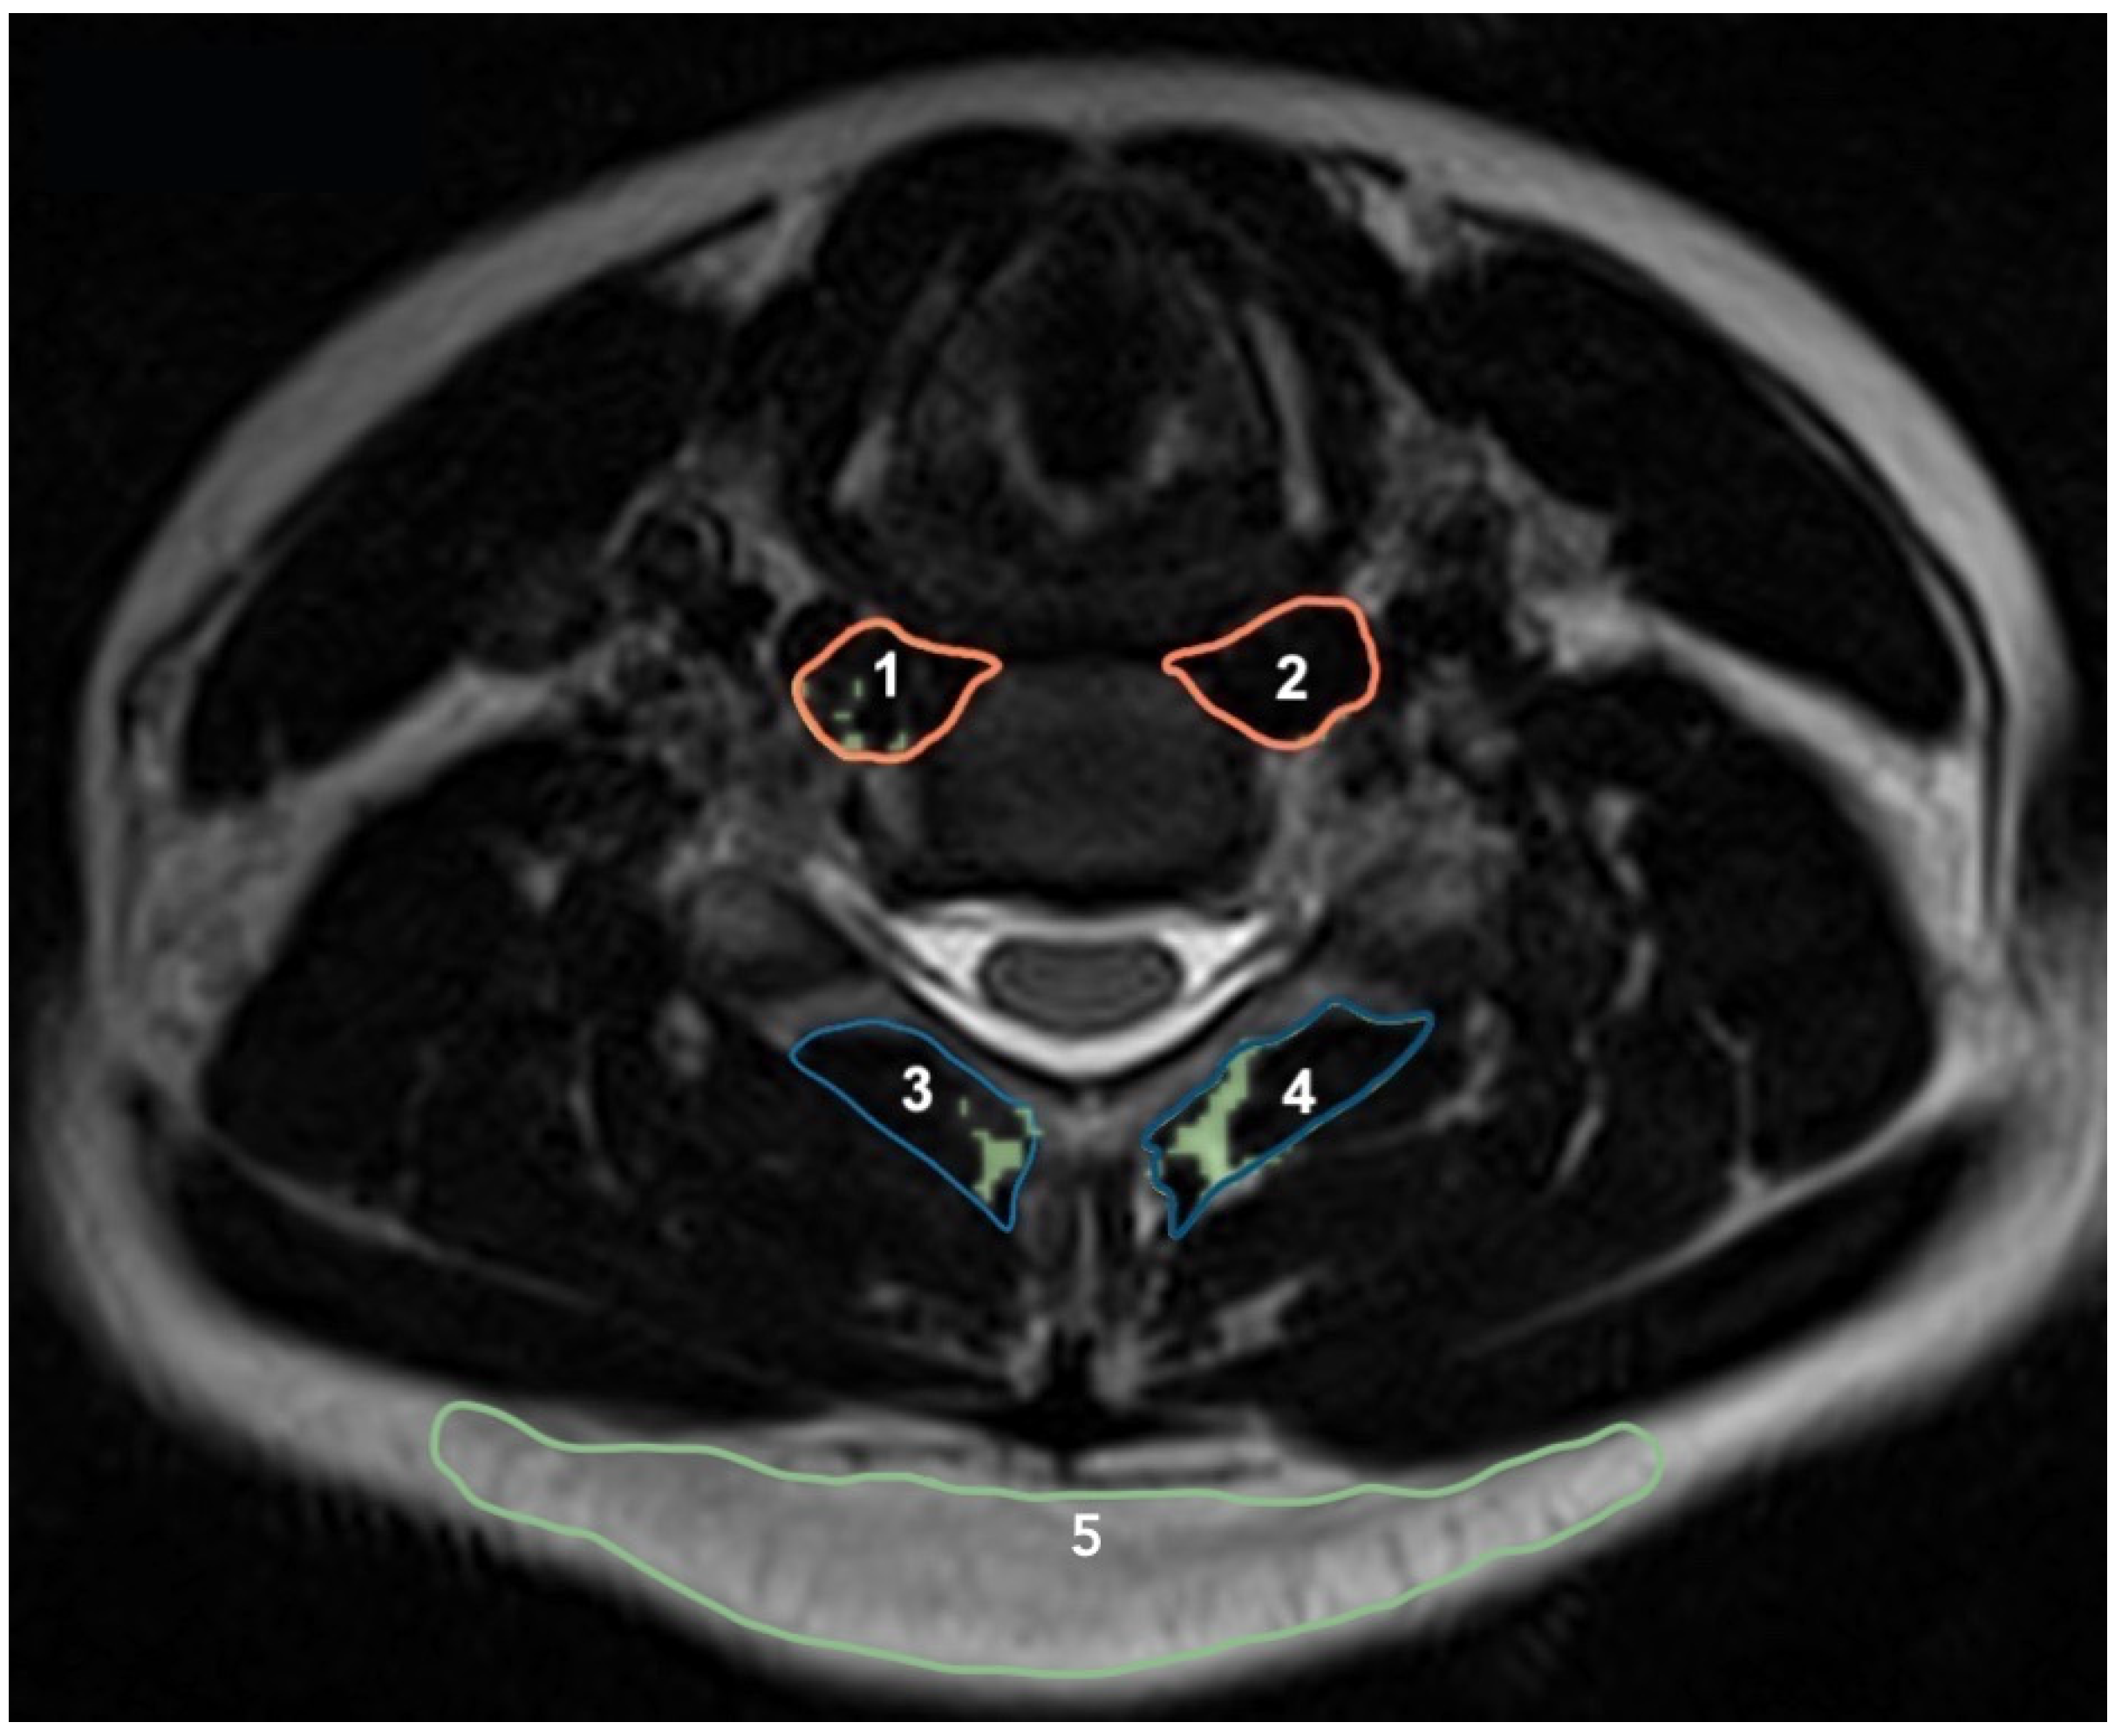

2.3. Cranio-Cervical Flexion Test